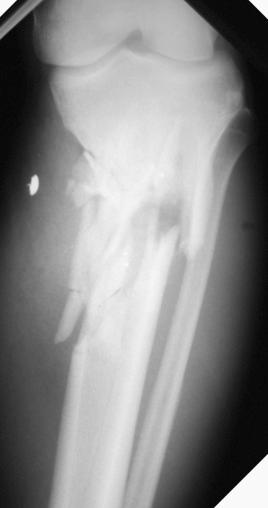

Any condition increasing the content or reducing the volume of a compartment could lead to compartment syndrome, but the most prevalent cause of compartment syndrome is trauma associated with a fracture. In the cases of fracture, energy from the trauma is dissipated into the bone and muscle, inducing intracellular swelling at the site of the trauma. The fracture site is also susceptible to hematoma after the injury, further amplifying the problem by increasing the volume and, therefore, the pressure of the compartment. High-energy tibial fractures are the most common type of injury associated with compartment syndrome, more specifically, bicondylar plateau fractures and segmental or comminuted tibial shaft fractures ( Figs. 17.2 and 17.3 ). ACS has been reported to complicate tibia fractures in as few as 1% to 9% of all cases and as high as 24% of polytrauma patients. However, it is important to consider that compartment syndrome can also develop secondary to arterial injury, occlusions, reperfusion injury, crush injuries, prolonged malposition, burns, electrocutions, snake venom, stressful athletic activity, contusions, and infiltrations from intravenous (IV) sites. There is also the potential for a compartment syndrome to arise from postresuscitation systemic inflammatory response syndrome after massive blood and fluid resuscitation.

Fig. 17.2, This radiograph shows a comminuted bicondylar plateau fracture. This type of high-energy injury has a high risk of developing acute compartment syndrome.